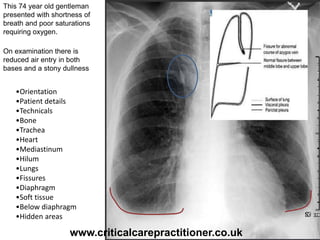

This 74 year old gentleman

presented with shortness of

breath and poor saturations

requiring oxygen.

On examination there is

reduced air entry in both

bases and a stony dullness

•Orientation

•Patient details

•Technicals

•Bone

•Trachea

•Heart

•Mediastinum

•Hilum

•Lungs

•Fissures

•Diaphragm

•Soft tissue

•Below diaphragm

•Hidden areas